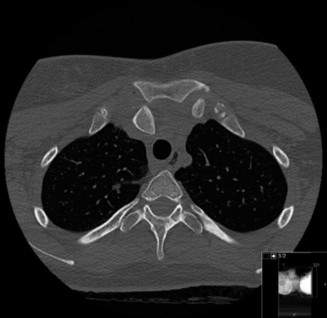

Standard radiography includes an anteroposterior view of the chest and a Serendipity view. The Serendipity view is obtained with the patient supine and the x-ray beam angled 40 degrees cephalad, centered on the manubrium. This view allows for comparison of the bilateral medial clavicles. In an anterior dislocation, the affected clavicle will appear superior to the uninjured side. In a posterior dislocation, the affected clavicle will appear inferior.

Despite the utility of the Serendipity view, computed tomography is the gold standard for evaluating sternoclavicular joint pathology. A CT scan of the chest with intravenous contrast should be obtained for all suspected posterior dislocations. Axial, coronal, and sagittal reconstructions clearly delineate the direction of displacement, the presence of physeal fractures in younger patients, and the relationship of the medial clavicle to the retrosternal vascular and aerodigestive structures. A CT angiogram is strongly recommended to rule out intimal tears, pseudoaneurysms, or direct compression of the great vessels.